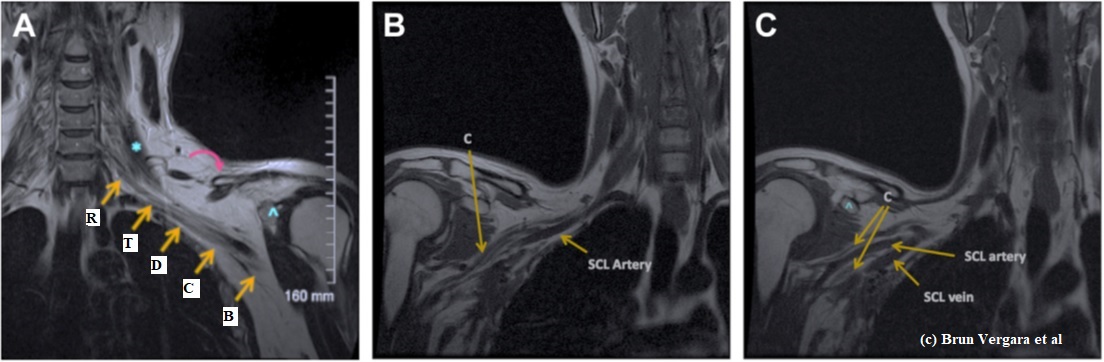

Results

Picture1

Figure 1. PRE > MID. Paired grey matter (GM) CVR difference map expressed in t-values (paired t-test; n=16; p<0.05). Significant decreases in CVR are shown in the left putamen and bilaterally in the cingulate and paracingulate gyrus. Images are in MNI space.

Figure 2. Average (A) PRE (n=18), (B) MID (n=18), and (C) POST (n=16) GM CBF expressed in mL/100g/min. Images are in MNI space.

Discussion

• Our results demonstrate that nonconcussive head impacts may lead to decreased CVR and possibly increased CBF, suggesting vascular dysfunction2 and compensatory hyperemia7